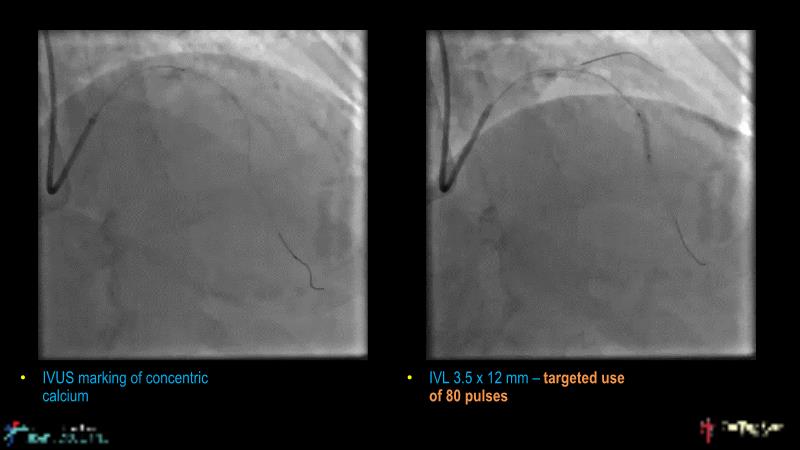

This session is recommended for you if you are seeking insights into the advantages of using IVUS imaging over visual assessment for better outcomes in left main bifurcation procedures. Discuss with experts the benefits of using RotaCUT in lesion preparation for left main bifurcation and explore the impact of high radial strength stents on the procedure's success.

• To understand why the use of IVUS imaging is different from seeing with experienced eyes to achieve improved left main bifurcation outcome

• To see advantages of RotaCUT as part of lesion preparation in left main bifurcation